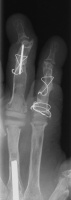

For the second stage of her reconstruction, the index proximal phalanx did not have adequate dorsal cortex to support an implant arthroplasty, and bone graft from the metacarpal head was used to reconstruct this.

Final radiographs, three months postoperative.